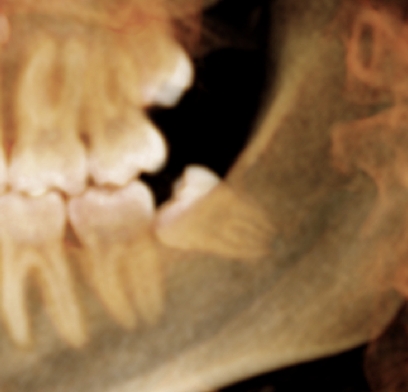

Impacted Wisdom Teeth (Third Molars)

Wisdom teeth or third molars are the last teeth to come into the mouth. They emerge in your mouth from ages 15-21. When a tooth doesn’t fully emerge properly and is stuck under the gums or bone, then it is called “impacted.” Impacted wisdom teeth can cause issues as they try to come in, including infection and pain. They can also affect the health of your second molars.

We recommend wisdom teeth be removed in adolescents (ages 15 to 21) in order to prevent future problems from occurring. Occasionally, they are removed earlier if they are impeding the normal emergence of the second molars. Typically, wisdom teeth are easier and safer to remove when they are partially formed. As they grow longer and your jaw bone becomes denser with age, then their removal can be more traumatic, and have more risk, thus increasing the chances for complications.